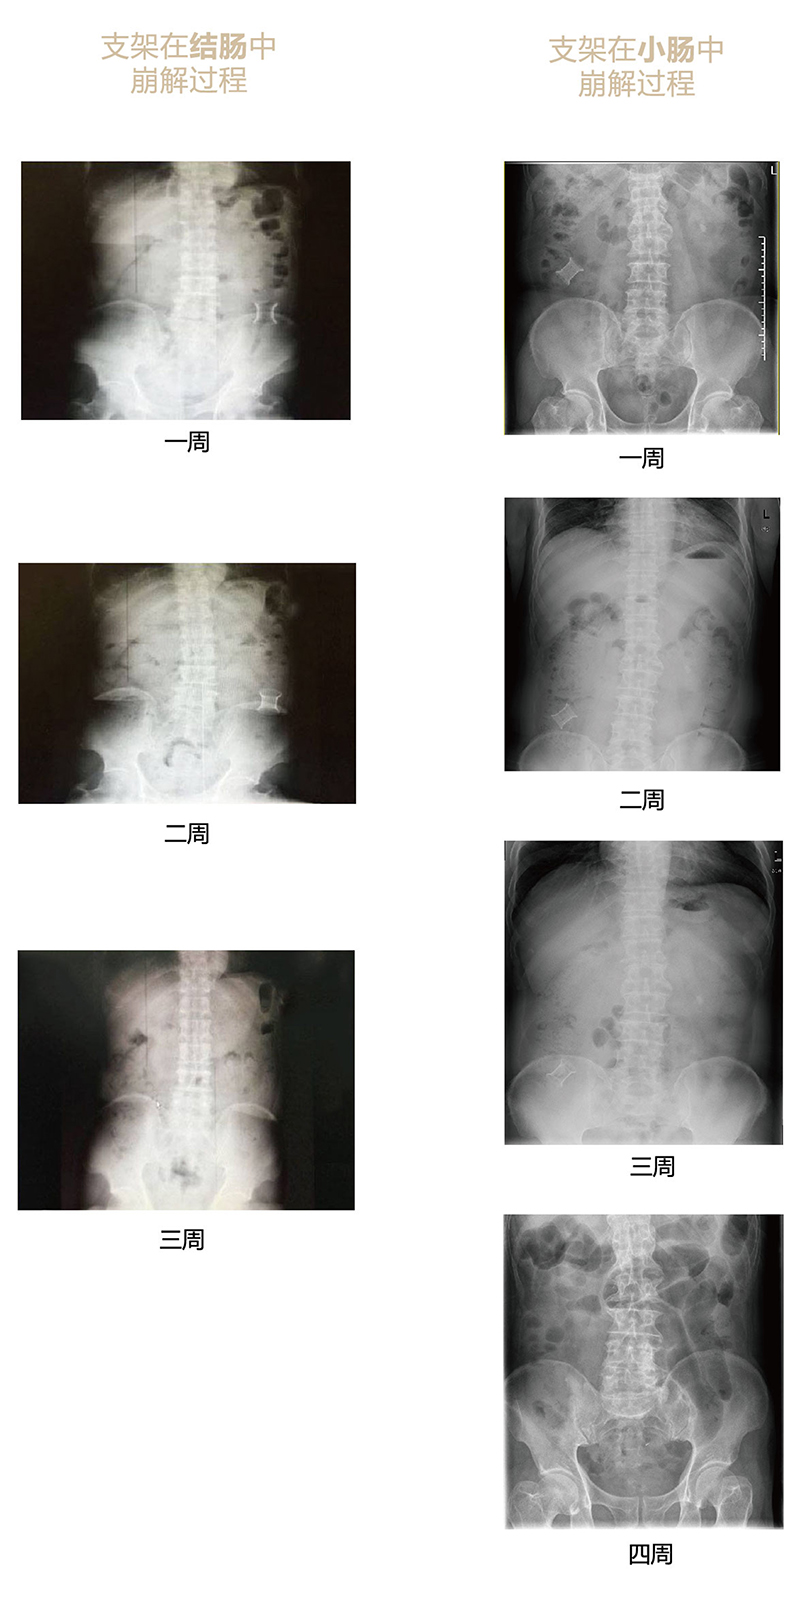

“可崩解腸道吻合器”由聚乙醇酸(PGA)與硫酸鋇按重量比7:1混合注塑制成,在X線下顯影,可動(dòng)態(tài)追蹤可崩解腸道吻合器(支架)在腸道內(nèi)崩解過程。

為解決該問題,蔡秀軍教授在“支架法空腔臟器吻合技術(shù)”的理念基礎(chǔ)上,又發(fā)明了“蔡氏腸轉(zhuǎn)流術(shù)”,這是一種應(yīng)用“可崩解腸道吻合器HB型(可崩解腸轉(zhuǎn)流支架)”(發(fā)明專利號(hào):201910794214.3),的支架法腸道轉(zhuǎn)流術(shù),此創(chuàng)新術(shù)式既能保護(hù)低位吻合口,更避免了回納術(shù)。可崩解腸轉(zhuǎn)流支架在直腸癌根治術(shù)中植入遠(yuǎn)端回腸,可確保完全阻斷腸腔,用腸造瘺管在轉(zhuǎn)流支架近端行腸造瘺,起到完全轉(zhuǎn)流的作用。腸轉(zhuǎn)流支架在二至三周內(nèi)逐漸崩解,并在四周內(nèi)完全排出體外,恢復(fù)腸道通暢后拔除造瘺管,避免了傳統(tǒng)造口回納的二次手術(shù)。該創(chuàng)新術(shù)式具有方法簡(jiǎn)單、吻合時(shí)間短、人體內(nèi)無異物永久殘留、不破壞吻合口粘膜下血管,并能預(yù)防吻合口漏、可避免人工肛門留置及二次手術(shù)、治療周期可縮短至二至四周、患者生理心理創(chuàng)傷顯著減少。